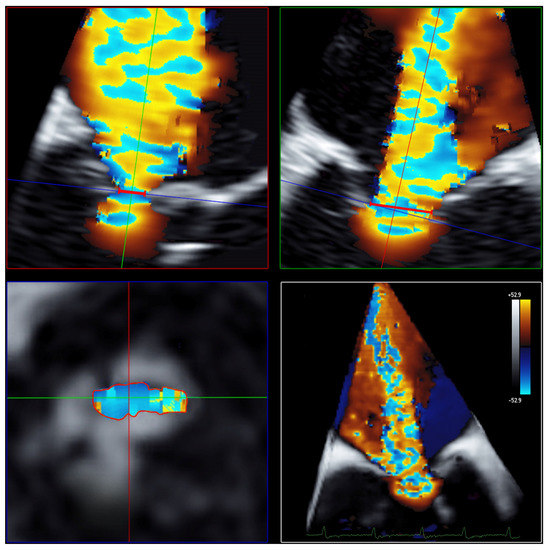

Measurements of 3D VCA and AROA were made using the full-volume 3D color Doppler datasets with the recommended limiting velocity of 50–70 m/s. The 3D VCA was planimetrically fitted to the minimum cross-sectional area of the regurgitation jet in the full-volume 3D color Doppler dataset (Figure 3). Considering the constraints of a curved plane, a manual measurement of the color Doppler of the cross-sectional plane was performed, excluding fractions of too-low velocities to determine the 3D VCA. Attention was paid to a constant setting of brightness and contrast and a fixed setting of color intensity at 50% values and smoothening.

Figure 3. Determination of 3D VCA using multiplanar reconstruction in the 3D color Doppler dataset. Echocardiographic images with 3 slice planes and 3D reconstruction (lower right) of the 3D color Doppler dataset (mid-systolic). Planimetric fitting of the 2 upper planes along the course of the color Doppler jet; third plane (lower left) adjustment orthogonal to planes along the jet and finding the minimal cross-section of the regurgitation jet using translation and tilting of the third plane; manual measurement of the minimal cross-sectional plane using outlining. Abbreviations: 3D = three-dimensional; VCA = vena contracta area.